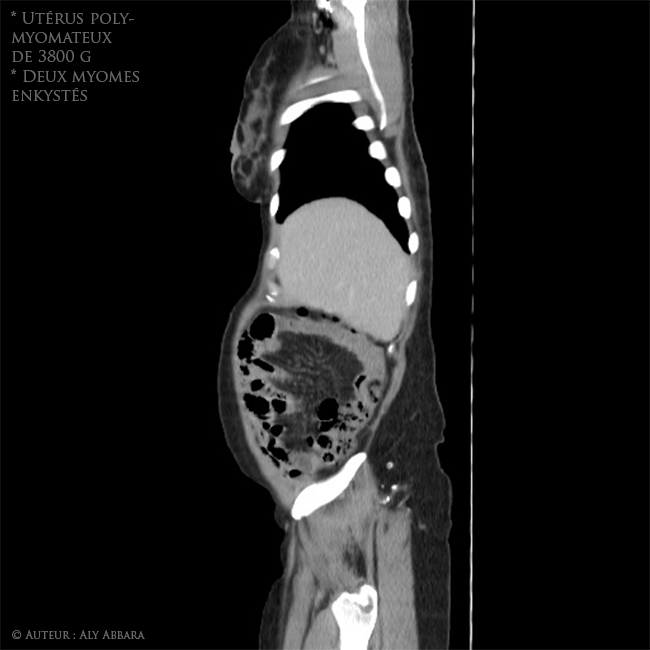

Utérus polymyomateux de 3800 g comportant deux volumineux myomes enkystés - Imagerie par scanner - coupes sagittales

Images Scanner (coupes sagittales) montrant un volumineux utérus polymyomateux pesant environ 3800 grammes et comportant deux myomes enkystés (kystes sous séreux utérins par dégénérescence kystique de fibromes) de 95 cm3 et 1661 cm3 de

volume